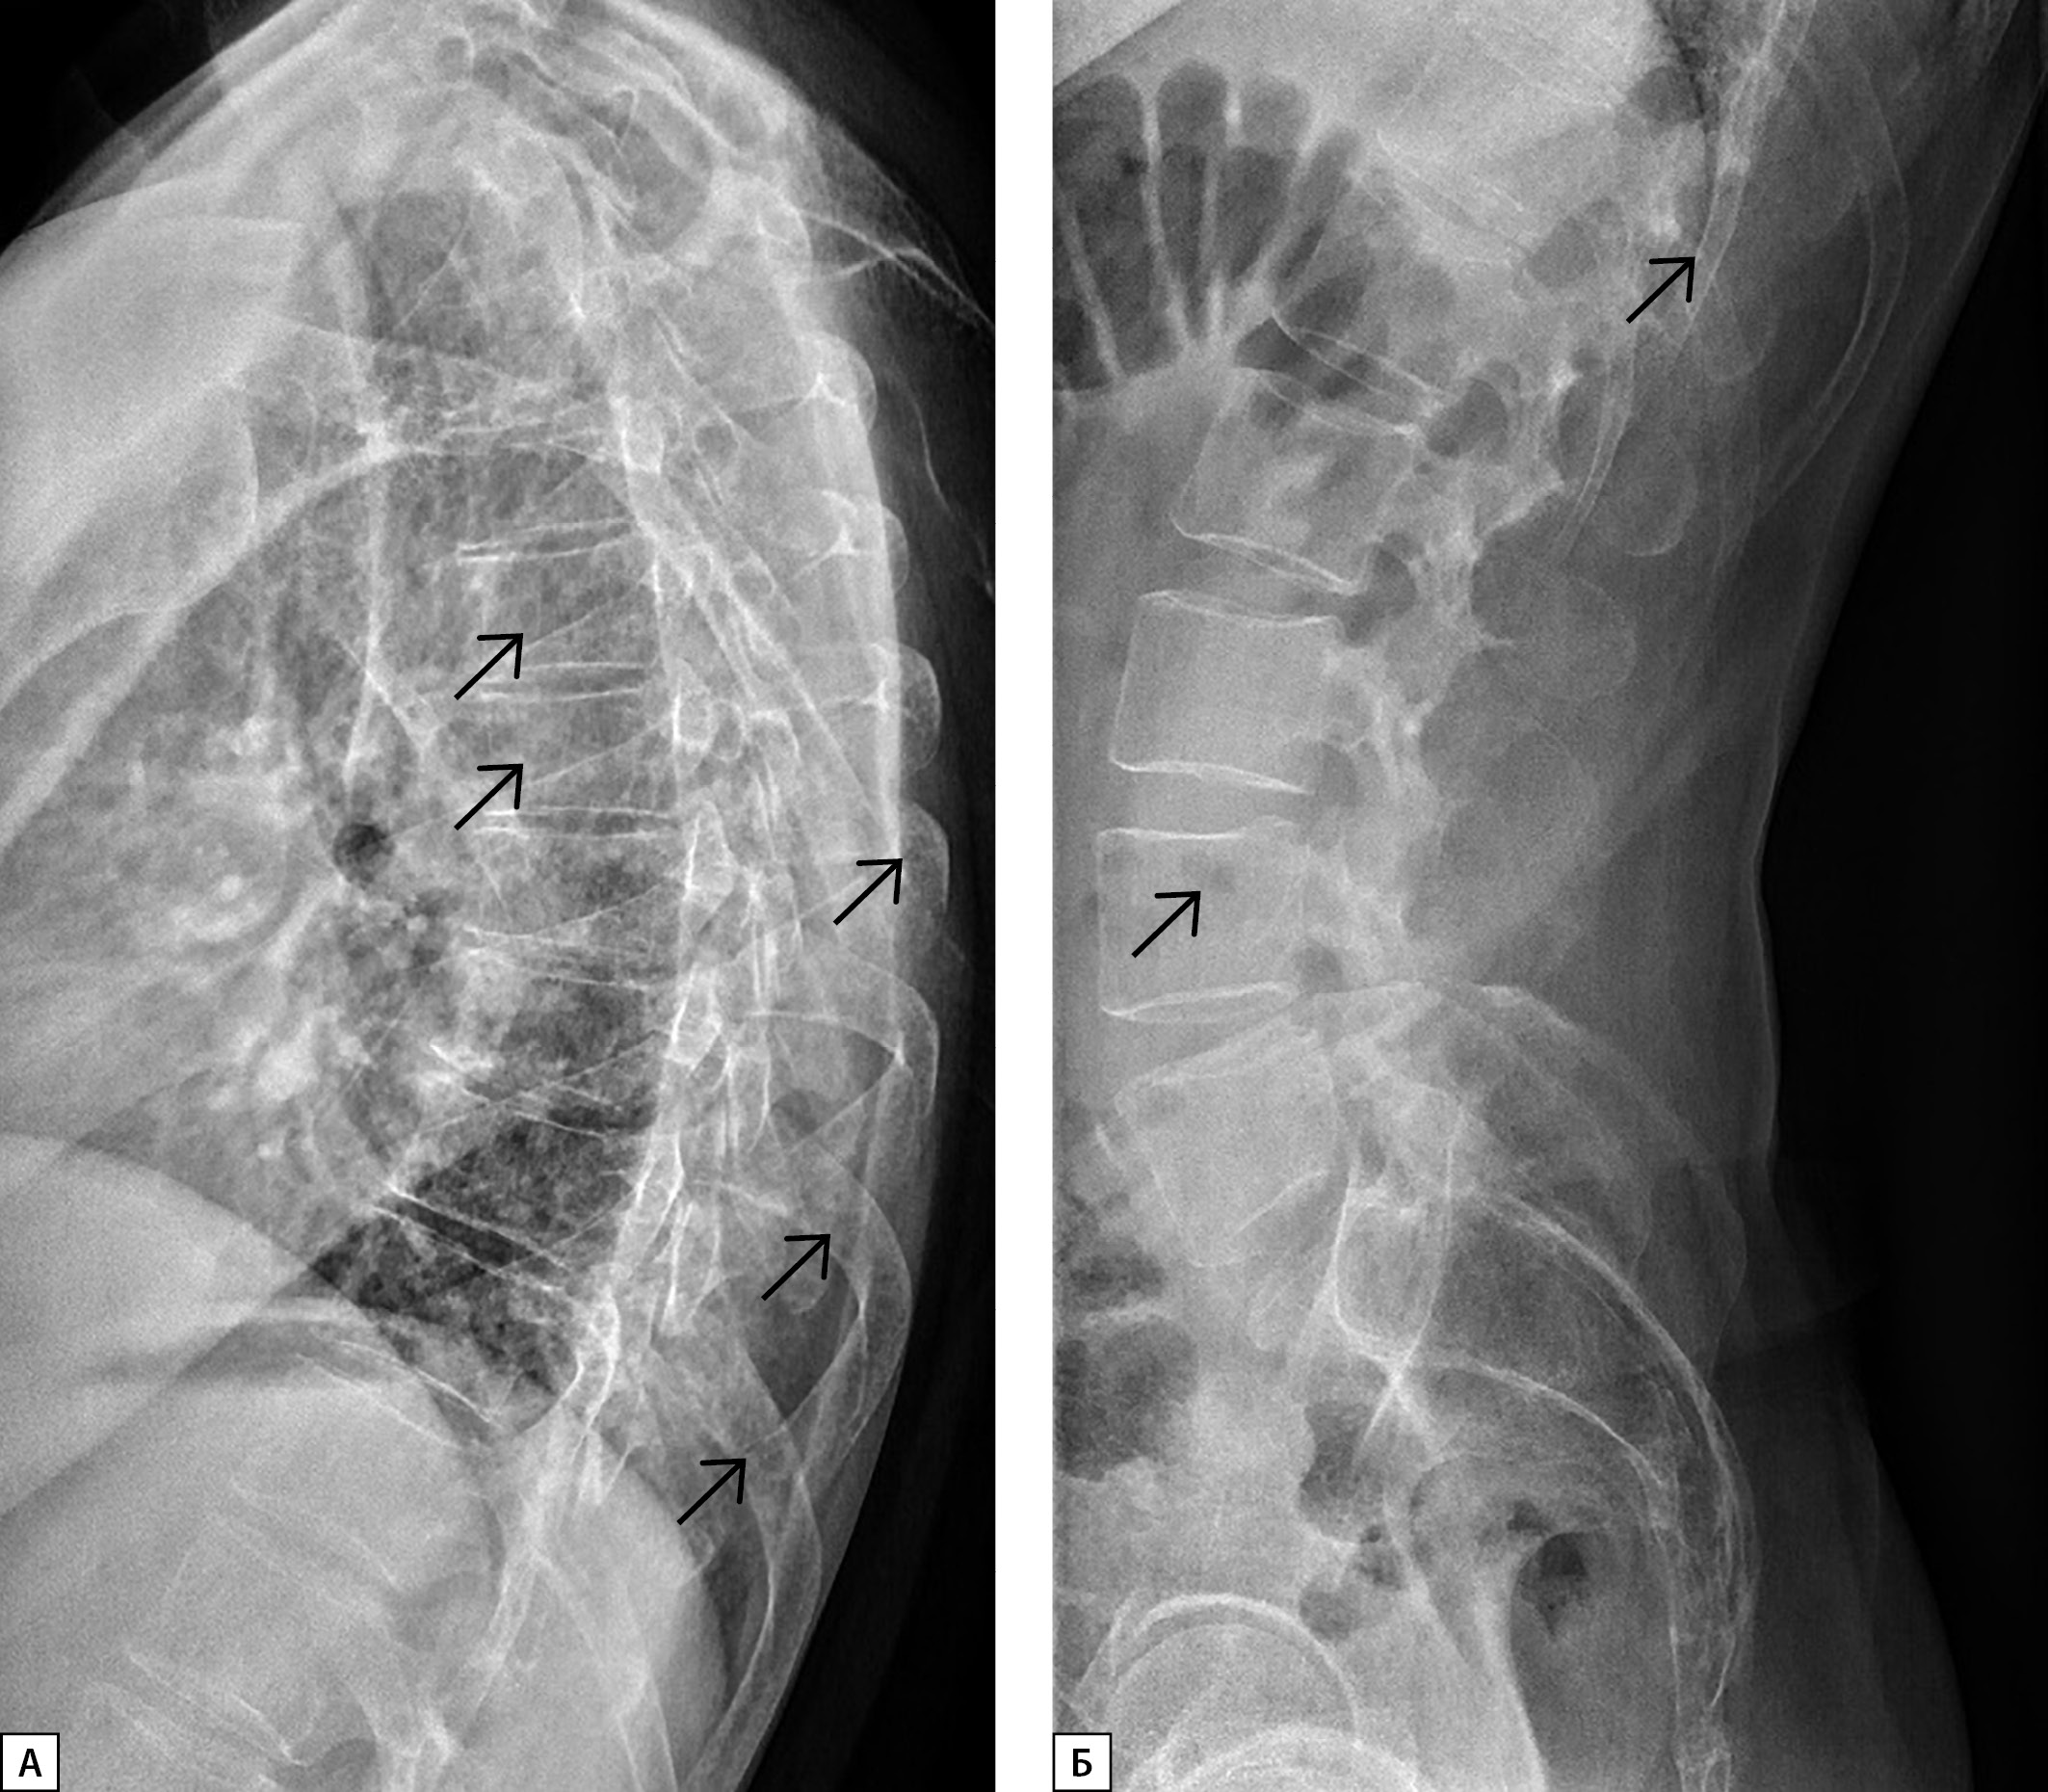

В связи с выявлением гиперкальциемии, гиперкальциурии на фоне референсных значений паратгормона, а также гиперпротеинемии и повышения СОЭ заподозрено наличие парапротеинемического гемобластоза. Проведена рентгенография черепа, по данным которой выявлены остеопороз костей свода черепа и множественные разнокалиберные очаги деструкции литического характера, местами с нечеткими контурами без периостальных наложений, диффузные во всех отделах, размерами от 2,9 до 13,5 мм (рис. 1). Данная рентгенологическая картина расценена как патогномоничная для множественной миеломы. Сходные изменения выявлены в телах и дужках шейных, грудных и поясничных позвонков (рис. 2).

Рисунок 1. Рентгенограмма черепа в боковой проекции пациента Я.

Стрелками обозначены очаги остеолизиса — симптом «дырявого черепа».

Figure 1. X-ray of the skull in the lateral projection of the patient I.

Arrows indicate foci of osteolysis — a symptom of a «leaky skull».